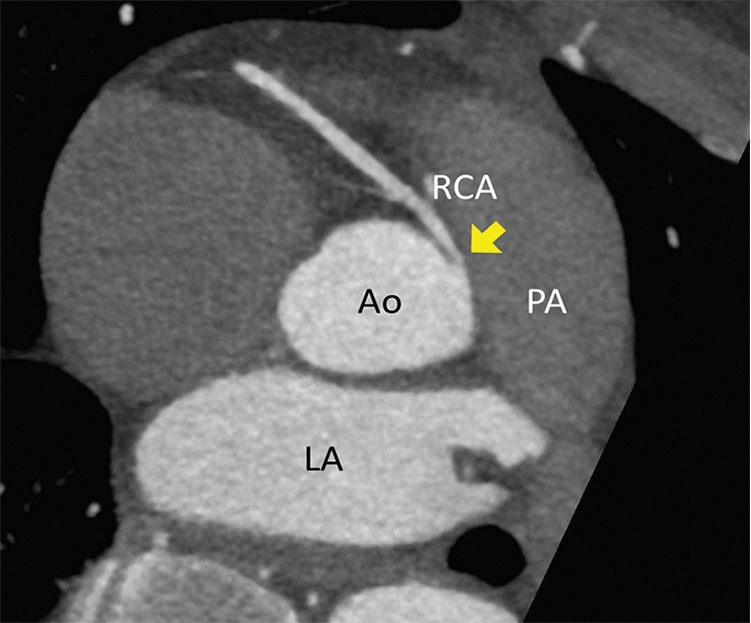

Clinical vignette 2: A 38-year-old man presents to an emergency department with atypical central chest pain. Serial troponins are negative, and a 12-lead electrocardiogram shows non-specific T wave changes. He has ongoing pain, is not deemed suitable for an “accelerated diagnostic protocol” pathway, and early computed tomography coronary angiography (CTCA) is performed after 100 mg oral metoprolol with 10 mg ivabradine, to achieve a heart rate of 59 beats per minute, allowing a low dose (< 1 mSv) scan. CTCA shows a normal left coronary system, but an anomalous right coronary artery origin arising from the contralateral cusp, with an interarterial course and a slit-like origin.6 This is a potentially life-threatening anomaly due to potential compression between the aorta and pulmonary artery resulting in sudden death;10 however, this may not have been diagnosed on functional testing (eg, single-photon emission computed tomography). Cardiac CT is the reference test for the assessment of coronary anomalies and coronary fistulae.6

CTCA axial view showing the RCA origin adjacent to the left main sinus and with an interarterial course between the aorta and pulmonary artery (arrow). Ao = aorta. Cx = circumflex. LA = left atrium. LAD = left anterior descending artery. LCC = left coronary cusp. LMCA = left main coronary artery. NCC = non-coronary cusp. PA = pulmonary artery. RCA = right coronary artery. RCC = right coronary cusp.